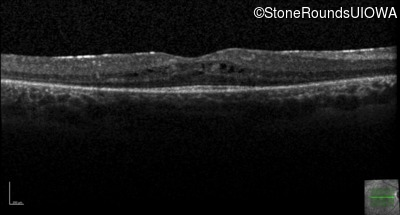

Optical Coherence Tomography - Right - 20/40 -2

Exemplar / OCT Stack